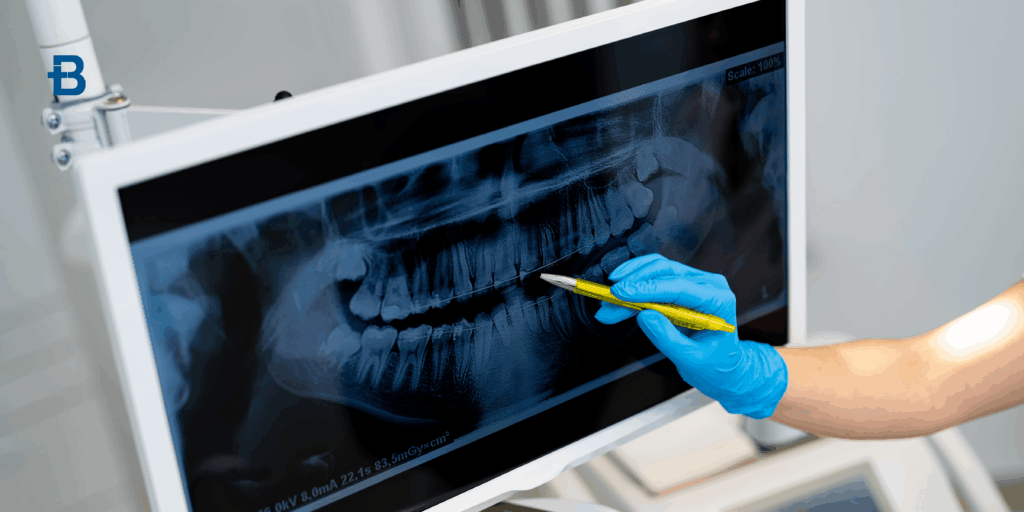

La TAC Cone Beam dentale è una tecnologia di imaging avanzata che sta rivoluzionando il campo dell’odontoiatria. Grazie alla sua capacità di ottenere immagini tridimensionali ad alta risoluzione, la TAC Cone Beam consente ai dentisti di visualizzare in modo dettagliato la struttura dentale e ossea del paziente, migliorando la precisione diagnostica e il trattamento. Ma cos’è esattamente questa tecnologia? In che modo si differenzia dalle radiografie tradizionali? E quando viene prescritta dal dentista? In questo articolo esploreremo a fondo la diagnostica 3D odontoiatrica, analizzando il funzionamento della TAC Cone Beam, le sue applicazioni e i vantaggi che offre ai pazienti. Cos’è la TAC Cone Beam La TAC Cone Beam dentale, conosciuta anche come Tomografia a Fascio Conico, è una tecnica di imaging avanzata che utilizza raggi X per produrre immagini 3D della bocca, dei denti e delle strutture circostanti, come ossa, nervi e tessuti molli. A differenza delle tradizionali radiografie, che offrono immagini bidimensionali, la TAC Cone Beam fornisce immagini tridimensionali che permettono ai dentisti di analizzare in dettaglio la struttura anatomica del paziente. Il dispositivo per la TAC Cone Beam dentale è costituito da un macchinario che emette raggi X in forma di cono, da cui il nome “Cone Beam”. Il paziente viene posizionato al centro del dispositivo, e durante la scansione il fascio di raggi X ruota attorno alla testa del paziente, acquisendo diverse immagini da diverse angolazioni. Successivamente, un software specializzato elabora questi dati per creare immagini 3D ad alta risoluzione. Queste immagini permettono di ottenere informazioni molto più precise rispetto alle tradizionali radiografie bidimensionali, facilitando diagnosi accurate e trattamenti mirati. Differenze rispetto alla radiografia Le principali differenze rispetto alla radiografia tradizionale risiedono nella qualità e nel tipo di immagine che viene acquisita. Mentre una radiografia convenzionale fornisce una visione bidimensionale delle strutture dentali e ossee, la TAC Cone Beam dentale offre un’immagine tridimensionale che permette una valutazione molto più completa e dettagliata. Immagini 3D vs 2D: La radiografia tradizionale fornisce solo una rappresentazione in due dimensioni delle strutture interne della bocca. Al contrario, la TAC Cone Beam crea una mappa tridimensionale, che consente ai dentisti di vedere le strutture da diverse angolazioni e di esaminare la posizione e la condizione di denti, ossa e nervi con maggiore precisione. Maggiore risoluzione e dettagli: La TAC Cone Beam è in grado di acquisire immagini con una risoluzione molto più alta rispetto alle radiografie tradizionali. Ciò consente ai professionisti di osservare dettagli fini, come la densità ossea, la forma delle radici dentali e la posizione dei nervi, che potrebbero non essere visibili con le radiografie convenzionali. Riduzione della distorsione: Le radiografie tradizionali possono presentare distorsioni, in particolare nelle immagini 2D delle strutture più complesse, come le radici dei denti. Con la TAC Cone Beam, questa distorsione è notevolmente ridotta grazie alla visualizzazione in 3D, che rende le immagini più accurate e affidabili. Esposizione ridotta a radiazioni: Un altro vantaggio significativo della TAC Cone Beam rispetto alle tradizionali TAC a spirale è che la quantità di radiazioni emesse è significativamente inferiore, rendendo la procedura più sicura per il paziente, pur mantenendo una qualità dell’immagine elevata. Quando viene prescritta La TAC Cone Beam dentale viene prescritta in specifiche situazioni cliniche, quando il dentista ha bisogno di informazioni più dettagliate e precise rispetto a quelle che possono essere ottenute con le radiografie tradizionali. Alcuni dei principali casi in cui viene prescritta includono: Implantologia dentale: La TAC Cone Beam è uno degli strumenti più utili nella pianificazione di impianti dentali. Fornisce una visione completa della struttura ossea e aiuta a determinare la posizione migliore per l’impianto, evitando danni ai nervi o ad altri elementi sensibili. Diagnosi di infezioni o malformazioni: Se un paziente presenta sintomi di infezioni ossee, cisti o altre anomalie strutturali, la TAC Cone Beam può aiutare a identificare la causa e a pianificare il trattamento. La visualizzazione 3D permette di vedere la dimensione e la posizione delle infezioni, facilitando la diagnosi. Patologie parodontali: Per valutare la gravità delle malattie parodontali e la perdita ossea associata, la TAC Cone Beam consente una visione precisa della struttura ossea del paziente, determinando l’estensione della malattia e aiutando a decidere il trattamento più adatto. Chirurgia orale e maxillo-facciale: In chirurgia orale, la TAC Cone Beam è fondamentale per la pianificazione pre-operatoria di interventi chirurgici complessi, come la rimozione di tumori o la correzione di anomalie strutturali della mascella e del viso. Valutazione dei denti del giudizio: La TAC Cone Beam è particolarmente utile per studiare la posizione dei denti del giudizio, specialmente quando sono inclusi o posizionati in modo anomalo, per evitare complicazioni durante l’estrazione. Trattamenti ortodontici: La diagnostica 3D odontoiatrica è anche importante per la pianificazione di trattamenti ortodontici complessi, poiché fornisce una visione dettagliata dell’allineamento dei denti e della struttura ossea, migliorando l’efficacia del trattamento. Vantaggi per il paziente La TAC Cone Beam dentale offre numerosi vantaggi sia per il dentista che per il paziente. Alcuni dei principali benefici includono: Maggiore precisione diagnostica: Le immagini 3D ad alta risoluzione permettono al dentista di esaminare dettagli che non sarebbero visibili con le radiografie tradizionali. Questo consente diagnosi più accurate e trattamenti più mirati. Riduzione dei tempi di trattamento: Poiché la TAC Cone Beam fornisce immagini rapide e dettagliate, il trattamento può essere pianificato in modo più efficiente, riducendo il numero di visite e i tempi complessivi di trattamento. Minore esposizione alle radiazioni: Rispetto ad altri tipi di TAC, la TAC Cone Beam emette una dose di radiazioni significativamente inferiore, riducendo i rischi per la salute del paziente. Miglioramento dell’estetica e della funzionalità: Grazie alla precisione delle immagini ottenute, la TAC Cone Beam consente di ottimizzare i trattamenti, come l’implantologia o la chirurgia maxillo-facciale, migliorando sia il risultato estetico che la funzionalità del sorriso. Maggiore comfort e velocità: La scansione con la TAC Cone Beam è rapida e meno invasiva rispetto ad altre tecniche di imaging, riducendo il disagio per il paziente. Prenota un consulto Prenota un consulto gratuito presso uno dei nostri centri Bludental per ricevere assistenza personalizzata dai nostri medici odontoiatri.